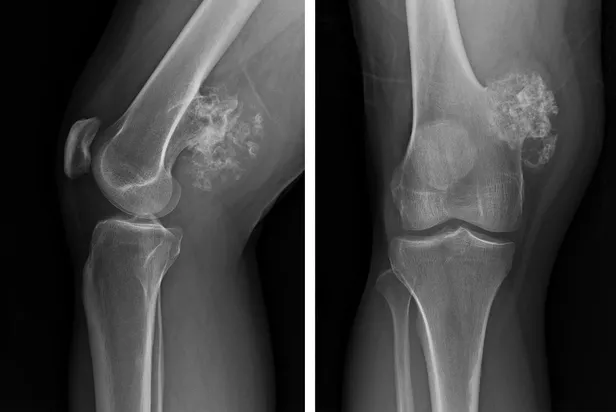

ŞİŞLİK:Hastanın özellikle diz, omuz ve kalça çevresinde düzensiz sınırlı, sert, hareketsiz ve hızlı büyüyen şişlik gelişir. Şişliğin ağrılı olması, kötü huylu olma açısından uyarıcı olmalı ve ağrı kesicilerle geçiştirilmeyip mutlaka en kısa zamanda hekime başvurulması gerekir.

KIRIK:Ağrı ve şişlik kadar sık görülmese de hem iyi hem de kötü huylu kemik tümörü kendiliğinden kemikte kırığa yol açabilir. Her ikisi de yerleştiği kemikte yıkıma neden olabilir.